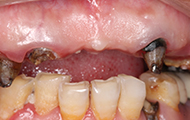

身边不少小年轻都美白牙齿,长达十年的血泪教训告诉我,科学方法、专业口腔太重要了,宣称7天牙齿美白的方法,千万别尝试,它让我感受到“有牙不能吃、牙疼又口臭”是多么痛苦的事,最终我不得不下决心拔掉半口残根烂冠,通过种上半口牙齿来重拾后半生的口福。

十年前的香港,烤瓷牙非常流行,它宣传能7天让牙齿变美变白,我也贪靓做了半口,无知的我厚厚把牙齿全打磨了,当时技术有限,不仅牙冠白的不自然,而且有金属线,烤瓷冠的边缘和我的牙齿密合不严,这十年来,我都是在反复的牙疼、敏感和口臭中度过,烤瓷牙冠给我带来的美丽远不如痛苦持久,这是我最后悔的是一件事。

在香港找了很多的口腔诊所,都说我的牙齿“病入膏肓”,要治疗的话只能全部拔掉种植,香港的消费实在很贵,所以我决定到深圳看看。好在遇到了深圳口碑比较好的口腔医院,他们帮我拆除了烤瓷牙冠,经过系列严苛检查,很耐心的跟我沟通牙齿问题,牙周炎症、蛀牙、牙髓炎等问题让我的牙齿已走到了末路,这被烤瓷牙吞噬的健康与口福,只能通过拔牙再种牙的方式来解决了。

今天要做的第一件事,就是把半口的烤瓷牙冠全部拆掉,然后做了洗牙和局部上药消炎,等炎症控制好了以后,再说拔牙和种牙,医生跟我说,如果牙周炎症不做处理,口内的细菌太多拔牙后会出现感染,洁牙的过程很舒服,洁牙师和助理搭配,洗的很细心。身边不少朋友都担心洁牙会让牙齿变松,我到今天才明白,牙结石是造成我牙周炎症的主要原因,烤瓷牙是导致我根尖周炎的罪魁祸首,哎……强烈建议大家日常的口腔保健,1年两次洁牙还是要做起来的,积极的预防比后期的治疗更重要!洁牙完牙齿会更干净,口气也会清新不少。

准备和烂牙说再见了,准备手术还是很紧张,手术在无菌室内进行,局麻后我能感知医生在口内的操作,开始心跳很快,我真的很怕拔牙,但不得不说医生的手艺好,没有我想象中的“敲砸撬”,就是觉得牙齿一酸一紧,就出来了。